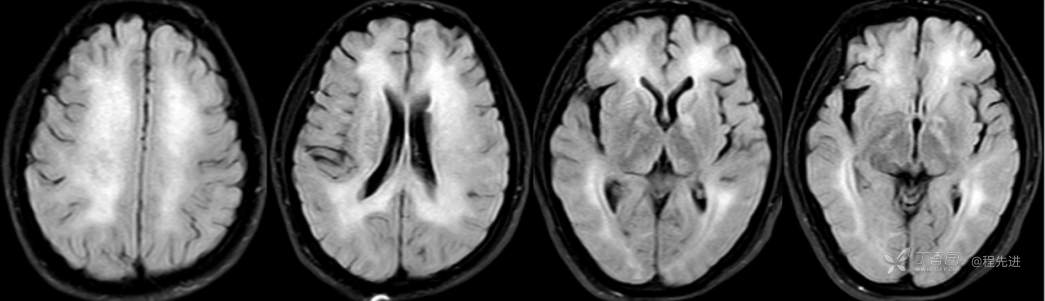

FLAIR

DWI